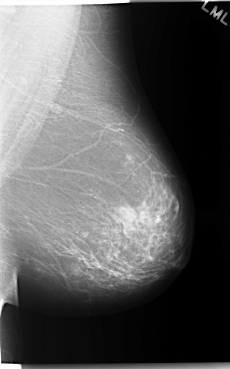

C_0045_1.LEFT_MLO

LEFT_MLO LINES 5904 PIXELS_PER_LINE 3672 BITS_PER_PIXEL 12 RESOLUTION 50 NON_OVERLAY